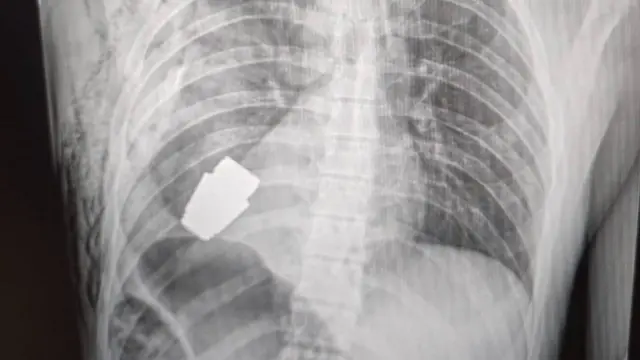

గాయపడిన జవాన్ ఛాతి లోపల ఇరుక్కుపోయి, ఎప్పుడైనా పేలిపోయే స్థితిలో ఒక చిన్న గ్రెనెడ్ను వారు విజయవంతంగా బయటకు తీశారు.

జవాన్ శరీరంలోని గ్రెనెడ్ 4 సెం.మీ వ్యాసార్థంతో, 275 గ్రాముల బరువుతో ఉంది. ఇది రష్యా వీఓజీ ప్రాంగ్మెంటేషన్ గ్రెనెడ్.